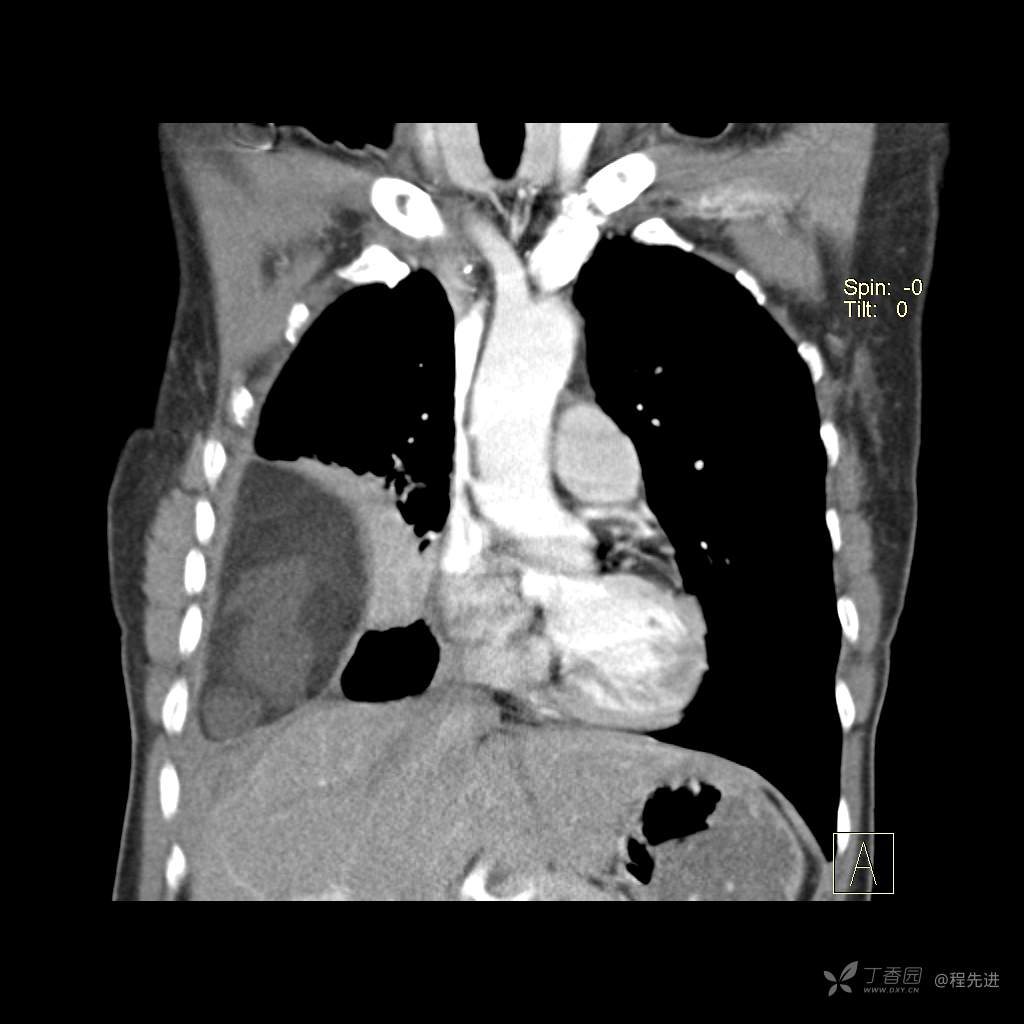

患者性别:女

患者年龄:51岁

简要病史:胸闷半年

肺淋巴管肌瘤病 (7)

乳糜胸 (8)